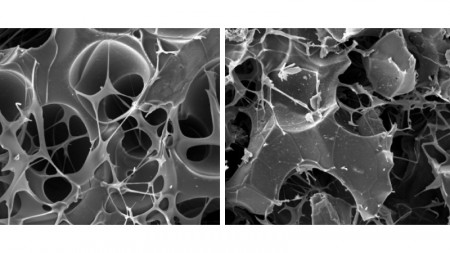

Imágenes de microscopía de la estructura de los biomateriales probados en la recuperación de fracturas durante el estudio; a la derecha, matriz de carbono; a la izquierda, la misma matriz asociada a nanografito (imagen: Daniela Franco Bueno et al.)

Para que este proceso ocurra efectivamente, es necesario regular factores como la microarquitectura de los biomateriales, de modo que presenten poros con tamaño y conectividad adecuados para permitir la entrada de vasos sanguíneos y células, así como el intercambio de nutrientes. También deben considerarse propiedades como la rigidez y la resistencia, para que sean compatibles con el tejido óseo. Todo ello se controla mediante métodos de producción en laboratorio y el uso de impresión 3D.